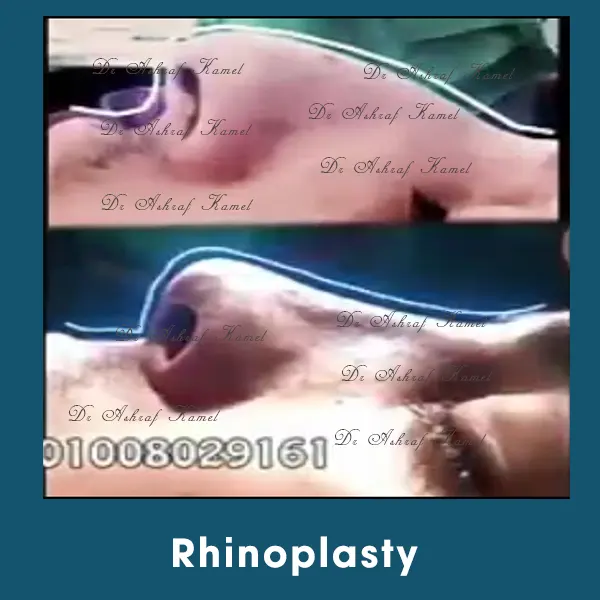

صور حالات مرضى

الخدمات

اشتهر بتقديم احدث تقنيات طب التجميل والجراحات التجميلية وعمليات تنسيق القوام، تكبير وتصغير وشد الثدي وتجميل الأنف وعلاج الترهلات، شد الذراعين و ازالة الترهلات، رفع الأرداف و علاج جراحات السمنة ونحت العضلات والـ6 باكس عالي التحديد، شفط الدهون بالفيزر والجي بلازما واحدث التقنيات بالخريطة الالكترونية، تجميل الجفون، تجميل الاذن وعلاج الاذن الوطواطية.